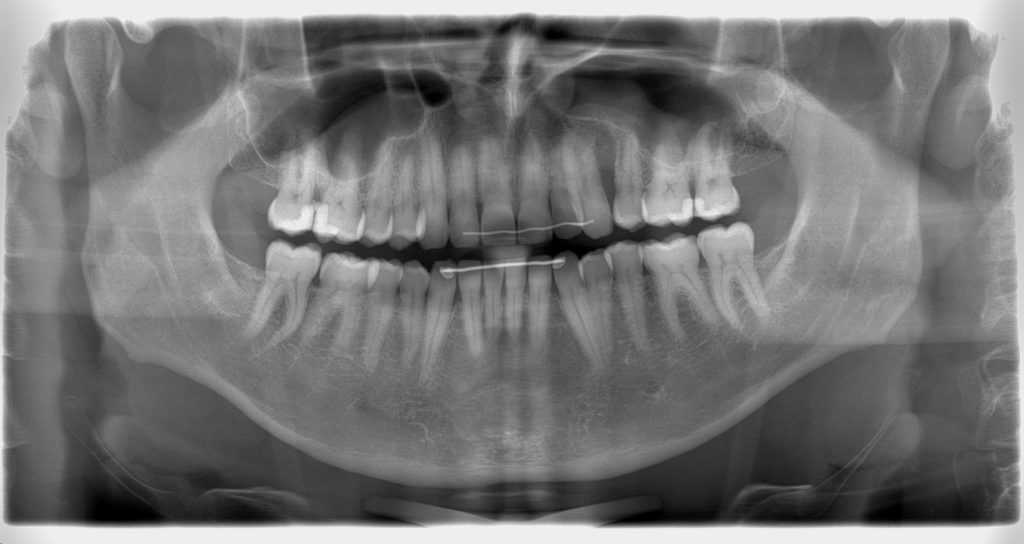

Baby Teeth Panoramic Xray. Recently in seattle, washington, a pediatric dentist was credited to saving a little girl’s life after she was losing an abnormal number of baby teeth at 4 years old. Image of the entire mouth including all teeth (including those that are not erupted yet), the upper and lower jaws, temporomandibular joints (tmj), nasal area, and sinuses. It is a two dimensional image that plays an important role in the examination and diagnostic process. Viewing development, position, and eruption of primary teeth so we can see all your child’s baby teeth and permanent teeth at one time3.

In teens and young adults we can monitor wisdom teeth. This particular type of digital image will show your orthodontist the following before starting you with braces. Viewing development, position, and eruption of primary teeth so we can see all your child’s baby teeth and permanent teeth at one time3. Image of the entire mouth including all teeth (including those that are not erupted yet), the upper and lower jaws, temporomandibular joints (tmj), nasal area, and sinuses. Recently in seattle, washington, a pediatric dentist was credited to saving a little girl’s life after she was losing an abnormal number of baby teeth at 4 years old. Fractures of the teeth and/or jaws can be seen when it is difficult to open your mouth2.

Image of the entire mouth including all teeth (including those that are not erupted yet), the upper and lower jaws, temporomandibular joints (tmj), nasal area, and sinuses. The jaw is a curved structure similar to that of a horseshoe. Taken at specific phases to monitor growth and development, identify extra and missing teeth, impacted teeth, as well as cysts and tumors. We usually take a panoramic xray when permanent teeth start to appear (approxiomately 6 yr. They are also used for planning orthodontic treatment and to evaluate growth and development. Although baby teeth are temporary, in order for healthy constants to form, they must be treated.

Old) so we can check to make sure that all permanent teeth are developing normally underneath the baby teeth. It is a two dimensional image that plays an important role in the examination and diagnostic process. They are also used for planning orthodontic treatment and to evaluate growth and development. The jaw is a curved structure similar to that of a horseshoe. We usually take a panoramic xray when permanent teeth start to appear (approxiomately 6 yr.

Old) so we can check to make sure that all permanent teeth are developing normally underneath the baby teeth. In teens and young adults we can monitor wisdom teeth. Here you can discover how panoramic radiography works, what to expect from the. Old) so we can check to make sure that all permanent teeth are developing normally underneath the baby teeth. They are also used for planning orthodontic treatment and to evaluate growth and development.